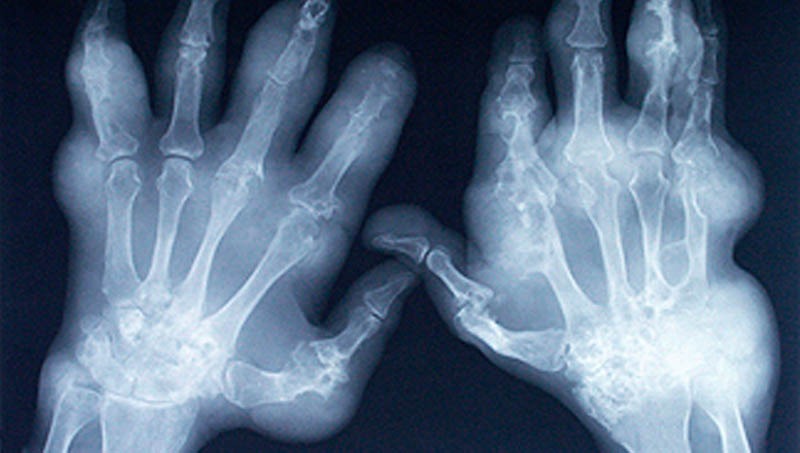

Jelentős összefogás keretében elindult az Arthritis betegség tájékoztató és segítségnyújtó kampány Békés megyében, a Pándy Kálmán Kórházban. A lakosság visszajelzése már az első hetekben igen pozitív. Mellékelünk egy tesztfeladat-sort, mellyel bárki megtudhatja, szükséges-e további kivizsgáláson részt vennie, veszélyeztetett-e, további lépéseket kell-e tennie egészsége érdekében.